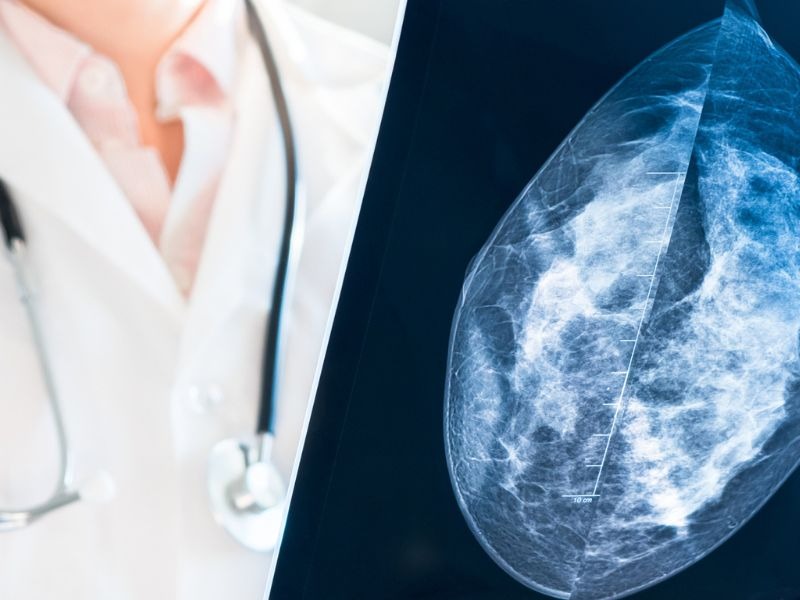

Chụp Mammography: Phương pháp tầm soát ung thư vú phổ biến

Chụp Mammography (hay X-quang tuyến vú) là phương pháp 'tiêu chuẩn vàng' trong việc tầm soát và phát hiện sớm ung thư vú.

1. Chụp Mammography là gì?

Chụp Mammography - hay còn gọi là chụp X-quang vú, là một kỹ thuật chẩn đoán hình ảnh y khoa sử dụng hệ thống tia X với liều lượng thấp để quan sát cấu trúc bên trong tuyến vú. Chụp Mammography đóng vai trò quan trọng trong việc phát hiện sớm và chẩn đoán các bệnh lý ở vú, đặc biệt là ở phụ nữ.

Chụp Mammography là là chụp X-quang vú